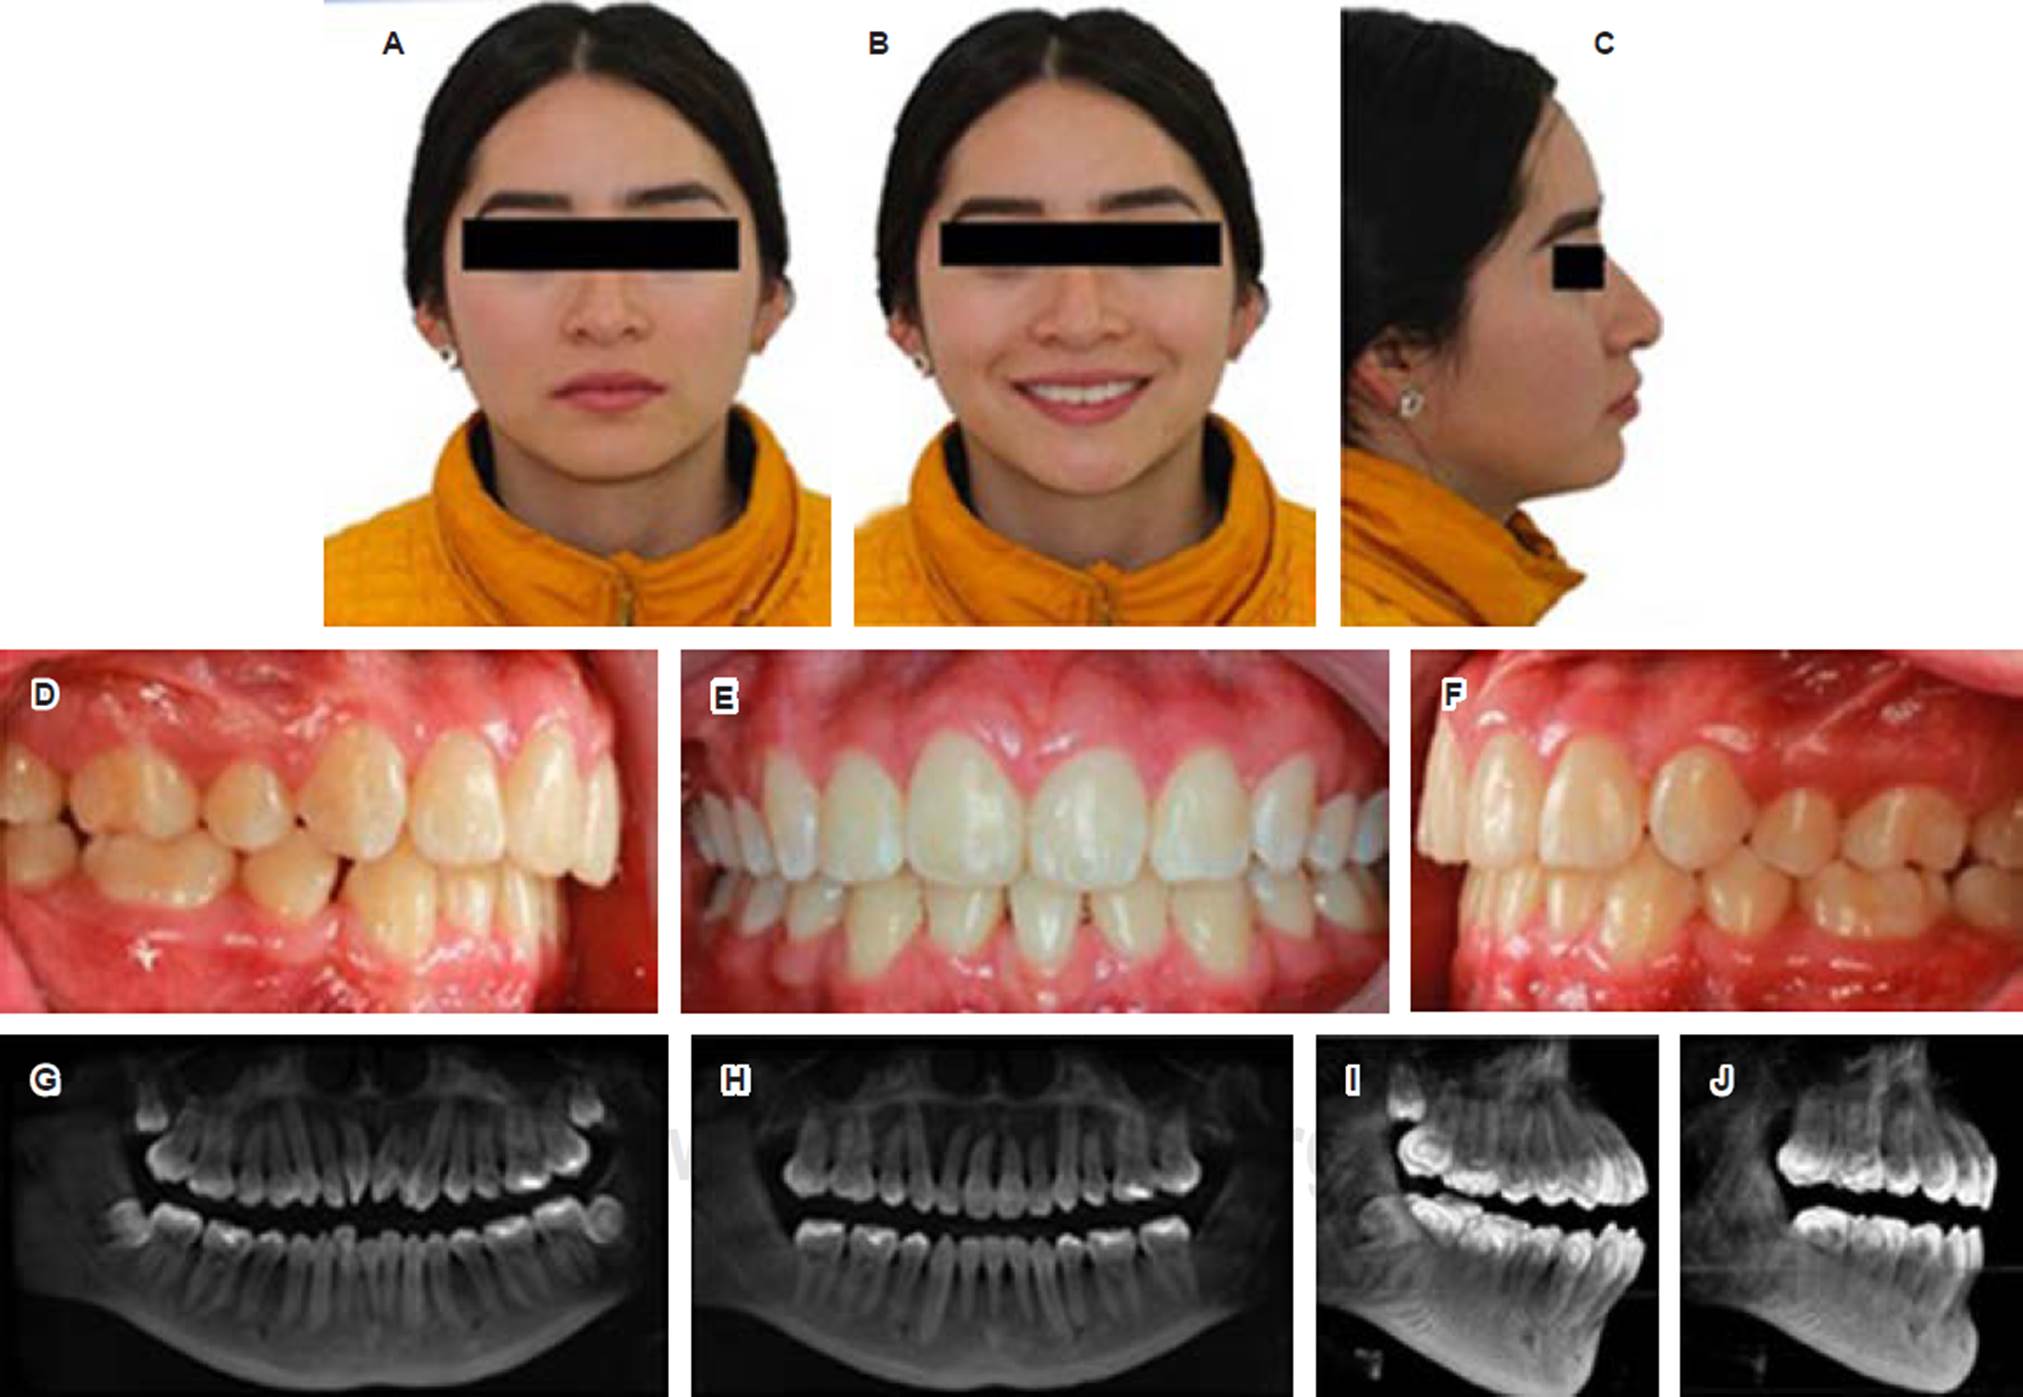

Paciente femenino de 16 años de edad procedente de San Martín Texmelucan, Puebla, con motivo de consulta «no me gustan mis dientes»; es una clase II esquelética, hiperdivergente, perfil facial ortognático, perfil labial convexo, clase molar I bilateral, clase ca nina II bilateral, presenta apiñamiento severo en maxilar y mandibular, no refiere ningún hábito. Al examen clínico extraoral, en su fotografía de frente (Figura 1A) se observa una paciente aparentemente simétrica y normoprósopo. En su fotografía de sonrisa (Figura 1B), la línea media dental superior coincide con la línea media facial (LMF) y la inferior desviada 2 mm a la derecha respecto a la LMF. En la foto de perfil (Figura 1C) presenta un perfil facial ortognático y un perfil labial convexo.

Figura 1 A) Frente, B) de sonrisa, C) de perfil, D) modelo lateral derecho, E) modelo lateral izquierdo, F) intraoral lateral derecha, G) intraoral frontal, H) intraoral lateral izquierda, I) oclusal superior, J) oclusal inferior.

Estudios intraorales: en el análisis de modelos y fotografías intraorales se diagnosticó a la paciente como clase I molar bilateral, clase II canina bilateral (Figura 1D-H), con un apiñamiento dental severo en ambas arcadas (Figura 1I y J).